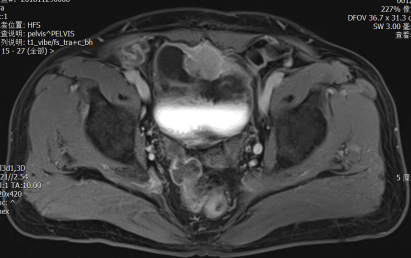

局部膀胱癌大致分为两类:一类,肿瘤的“根”没有突破膀胱的肌肉层,是为表浅的膀胱癌,预后大多数较好;另一类,肿瘤的“根”长的很深,长到了肌肉里面甚至突破膀胱长到膀胱周围的脂肪里面、侵犯到周围的器官,预后相对较差。后者一般要开大刀,做根治性膀胱全切。那么,是不是一旦发现必须马上做膀胱全切?手术之前要不要做全身化疗?

一方面,肌层浸润性膀胱癌的的患者可能已经出现了一些微小的转移灶,特别对于分期偏晚的,肿瘤恶性度高一些的病人。那么根治性手术前的全身化疗有助于消灭这些潜在的病灶;另一方面,有些膀胱肿瘤体积大,或者浸润的深度较深,手术前的全身化疗能够达到缩瘤降期的目的。据国外研究者报道,约一半的肌层浸润性膀胱癌患者对GC方案的新辅助化疗有反应,而约1/4的患者化疗后肿瘤完全被消灭。这样一来,有一部分不愿意做全膀胱切除的患者,甚至有保膀胱的可能。还有,肿瘤如果突破膀胱向外生长,直接行全膀胱切除,肿瘤残存的风险高,切缘阳性率高。一旦肿瘤残存,外科医生是非常头痛的,患者本人可能面临放疗、化疗甚至免疫治疗等挽救性治疗。而接受了手术的病人,再次化疗的风险相对更高。所以,为了把肿瘤切干净,也建议先做新辅助化疗。